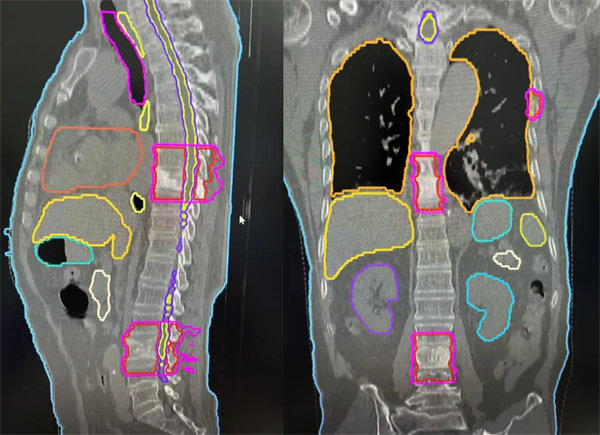

肋骨、胸椎、腰椎轉移灶的長靶區照射(紅色區域)

針對患者的病情,血液腫瘤風濕免疫內科副主任朱暉和放射治療科張世衡副主任醫師反復討論,最終確定長范圍、多病灶靶區的治療方案。由于患者及家屬對放射治療止痛效果的疑慮,科室反復多次和患者及家屬溝通:“張師傅,您放心吧,我們醫院的TOMO加速器是目前世界上最先進的放療機器之一,它的優點就是:TOMO有效治療范圍更大,最長可40CM*135CM,對于多發病灶可以在同一個定位區間內同時治療,正是TOMO這樣的特殊設計和功能,照射腫瘤的部位更精準、對周圍正常器官副作用小,而且每次治療之前都有CT圖像引導,可以根據病灶情況實時調整勾畫靶區,請您相信我們”。經過一番耐心地解釋說明,張師傅及家屬慢慢打消了顧慮,積極配合治療。在經過反復確認靶區、劑量及危及器官限值,科室討論后,一致認可此次放射治療的安全性和可實施性,放射治療科團隊加班加點,在兩天之內完成了制模,定位,靶區勾畫,計劃設計驗證,用最短的時間給張師傅安排了放射治療。血液腫瘤風濕免疫內科及放療主管醫生著重觀察患者對放療的反應,密切監測血常規、生化等指標,結合對癥支持治療,做好保駕護航。僅僅經過2次放療,張師傅腰背的癥狀就有了明顯的改善,晚上能安穩睡到天亮,直至5次放療結束患者未出現不可耐受的副作用。

患者及家人喜悅的表情給了我們最大的肯定。TOMO放療設備作為目前世界上尖端的放射治療設備之一,具有高度的精準性和適應性,能夠顯著提高腫瘤治療的療效,長靶區照射一次解決問題。通過引入TOMO放療,開啟了腫瘤多學科綜合診療模式,提升了我院在腫瘤診療、疑難病例診療能力等方面的綜合實力,更好地滿足患者對高質量醫療服務的需求,同時,也將推動醫院在腫瘤防治事業上的高質量發展。